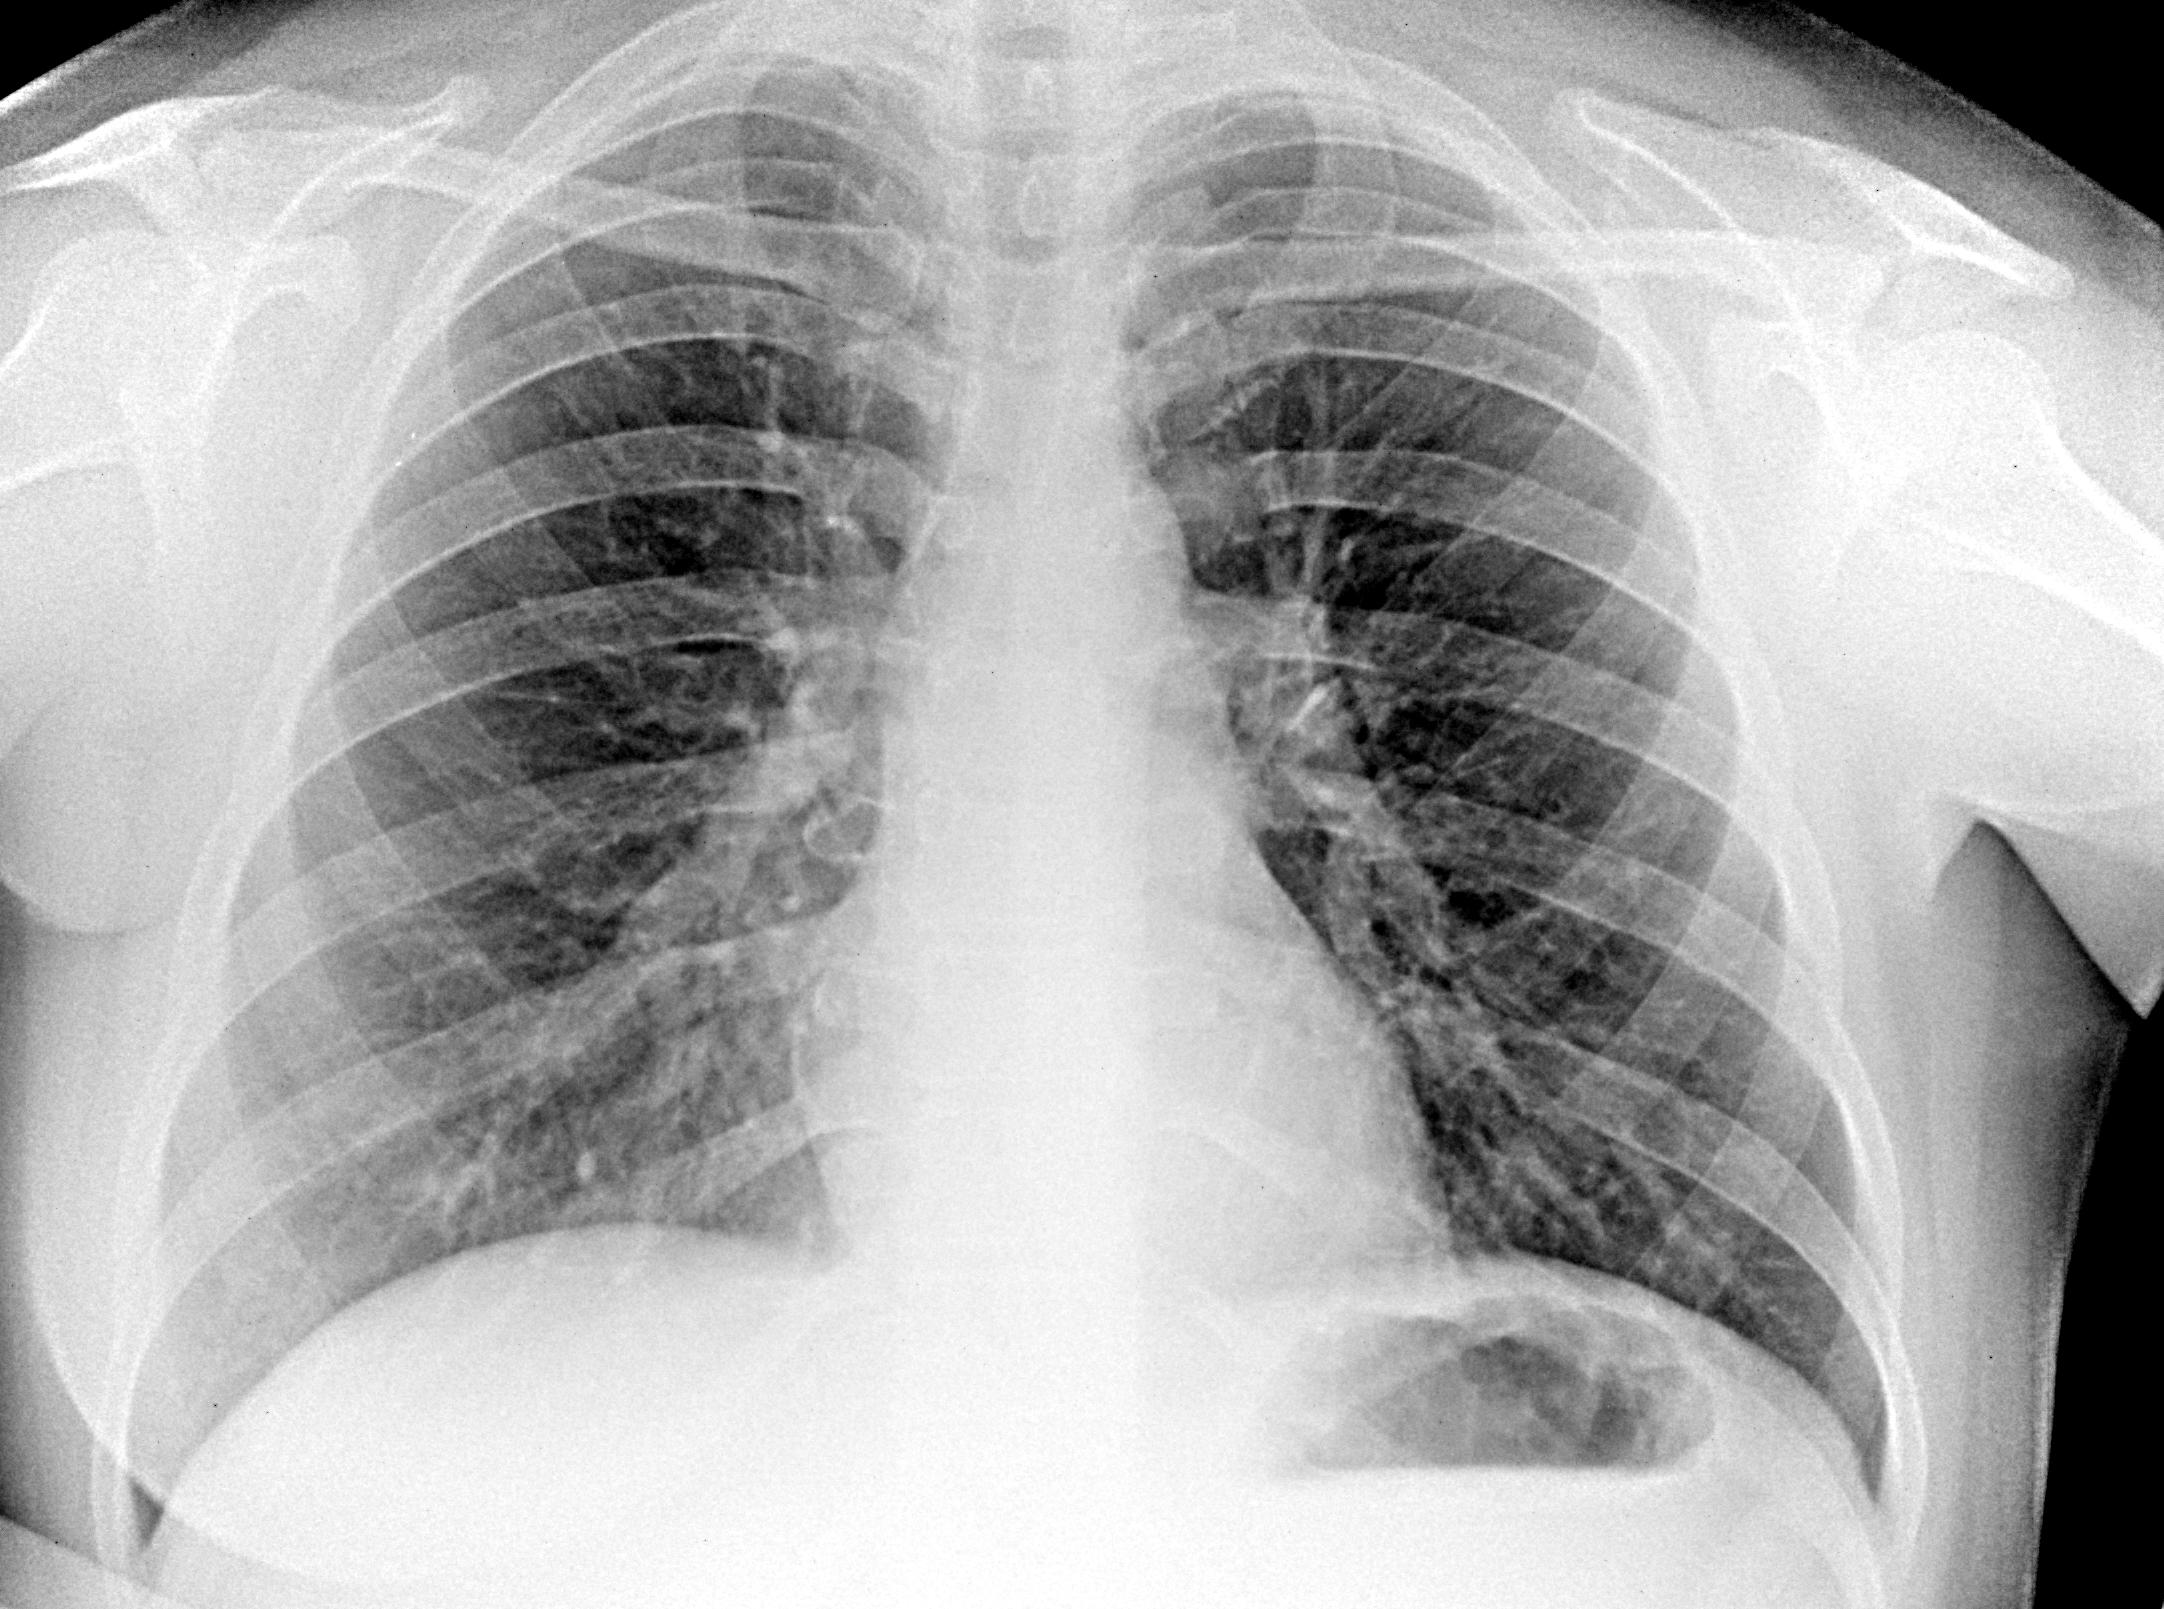

Проф флг, 1972 г.р , мастэктомия слева (cr) - изменения правого поперечного отростка позвонка на уровне тела пр корня. Остеопороз? Мтс? Скиалогия? Надо дообследовать? https://radiomed.ru/sites/default/files/styles/case_slider_image/public/user/18954/d94dde69-9d62-4f0b-a04e-a585f611e8dv1.jpg?itok=e0ahw8rW ID:47073 Fri, 18/04/2014 - 22:50 #1 тюрин Offline Last seen: 1 month 3 weeks ago Joined: 18.12.2009 - 17:23 Posts: 215 последний вариант Вашего ответа. я б на скопии покрутил. Fri, 18/04/2014 - 23:18 #2 Дмитрий Волегов Offline Last seen: 3 years 7 months ago Joined: 22.05.2013 - 00:32 Posts: 1148 Просветление объясняется отсутствием наложения сосудистой тени, в отличие от других поперечных отростков. Норма. Дообследовать не нужно. С Уважением, Дмитрий. Fri, 18/04/2014 - 23:35 #3 NIL Offline Last seen: 1 month 6 days ago Joined: 25.11.2013 - 20:50 Posts: 18208 Думаю, этот? Скиалогический эффект. Остальные поперечные отростки прикрыты чем-нибудь, а этот высунулся и режет глаз.Приложения: "Слушай всех, прислушивайся к немногим, решай сам".© Sat, 19/04/2014 - 11:01 #4 atexta Offline Last seen: 2 years 11 months ago Joined: 08.02.2014 - 18:41 Posts: 4842 Если сравнить с противоположной стороной-одинаковые, скиалогия Не нам судить… Sun, 20/04/2014 - 20:29 #5 JJ Offline Last seen: 11 years 6 months ago Joined: 03.04.2014 - 20:35 Posts: 102 если смущает, то лучше сделать обзорные снимки грудного отдела позвоночника - анамнез здесь нехороший

Просветление объясняется отсутствием наложения сосудистой тени, в отличие от других поперечных отростков. Норма. Дообследовать не нужно.

Думаю, этот? Скиалогический эффект. Остальные поперечные отростки прикрыты чем-нибудь, а этот высунулся и режет глаз.

Если сравнить с противоположной стороной-одинаковые, скиалогия

если смущает, то лучше сделать обзорные снимки грудного отдела позвоночника - анамнез здесь нехороший